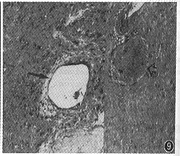

1.肿瘤CT增强影像表现特殊,可分为以下几类:(1)低密度区中伴团状高密度改变24个(图1),病理改变为在比较广泛分布的疏细胞区(Antoni B区)组织中,有相对集中分布的富细胞区(Antoni A区)(图2)。(2)弥漫点状改变20个,点状大小从1~4 mm不等,其密度不等。高密度CT值为60~80 HU,低密度为40~45 HU,两者CT值相差约20 HU。其中呈低密度点状4个;高密度点状4个;高、低密度混杂点状12个(图3)。此20个肿瘤中8个伴有1~2个形态不规则的低密度裂隙样变。高低密度混杂点状分布的病理改变为的Antoni A区、Antoni B区相互交错,分布均匀(图4)。低密度点状改变为比较广泛分布的Antoni A区或胶原基础上出现的零星分布的Antoni B区或微囊集中处,Antomi B区或微囊分布较集中时,即表现为低密度裂隙样改变。较广泛分布的Antoni B区伴少量Antoni A区或胶原则呈高密度点状改变。(3)低密度环伴中央弥漫不同密度点状改变5个,其中单纯为低密度点状或单纯为高密度点状各1个。此低密度环在病理上由Antoni B区组成。(4)中央低密度伴有环形改变8个(图5),环壁厚,环表现各异,其中表现为高、低密度混杂点状分布的3个,单纯低密度点状或高密度点状各2个,环与肌肉呈等密度1个。肿瘤中央的低密度区病理上由Antoni B集中区和(或)陈旧性出血区组成。(5)密度均匀的12个肿瘤中,等密度与低密度各5个,囊性变2个。在病理上等密度多由Antoni A区及胶原组成,Antoni B区较少,分散在Antoni A区及胶原间;而低密度肿瘤(图6)为均匀一致的Antoni B区及部分陈旧性出血组成,几乎无Antoni A区细胞(图7)。囊性肿瘤巨检时见黄色液体流出,囊壁上仍见典型Antoni A、Antoni B区改变。(6)增强特别明显的肿瘤3个,其中2个为弥漫点状改变(图8),1个为厚环。病理显示此3个肿瘤由丰富的Antoni A区组成,夹杂有微囊,而Antoni B区少见(图9),其中仅2个血供比较丰富。

图9 图8肿瘤病理学(HE ×40)表现,示肿瘤主要为Antoni A区,CT所示点状低密度区为微囊(黑箭)及陈旧性出血(空箭)